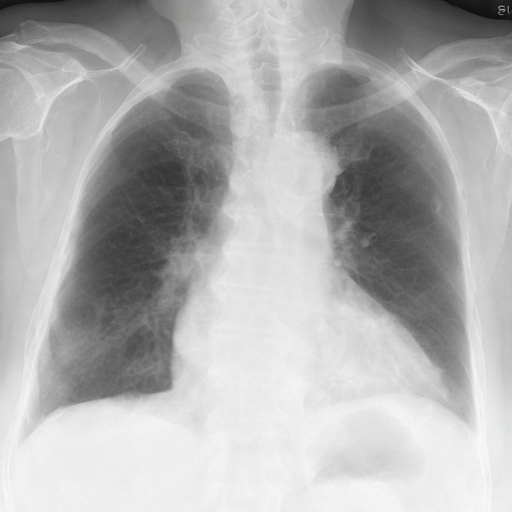

Let's load an example image of a patient with influenza.

For this example, we will remove the visual appearance of influence from the lungs, while preventing changes from happening to the rest of the image. To do this, we create a mask of the lung regions and use this as the edit_mask which defines the region we wish the editing prompt to be applied to. Since we want the rest of the image to remain unchanged, we use the inverse as the keep_mask which defines the region where edits are discouraged from taking place.

prompt = 'No acute cardiopulmonary process'